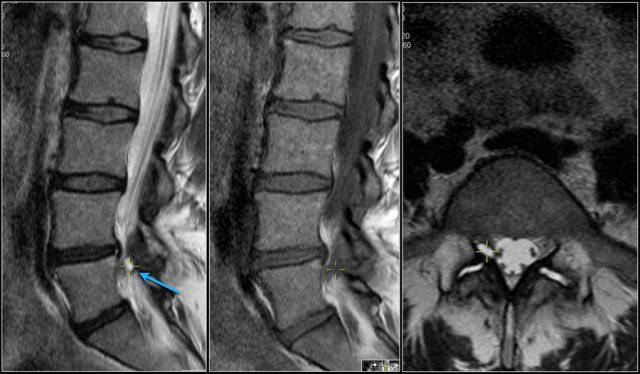

Here a disc herniation with upward migration.

By using the marker, you can correlate the abnormality on the T1W-image with the axial T2W-images.

On the T2W-image it is more obvious that this is a disc herniation.

The lower images are with the marker on.

you may have to enlarge the images to see it.

These foraminal disc herniations can be easily overlooked.

Notice how subtle the findings are on the axial T2W-images.

The herniated disc can be easily mistaken for the nerve root.

The sagittal T1W-image shows the upward migration of the disc.